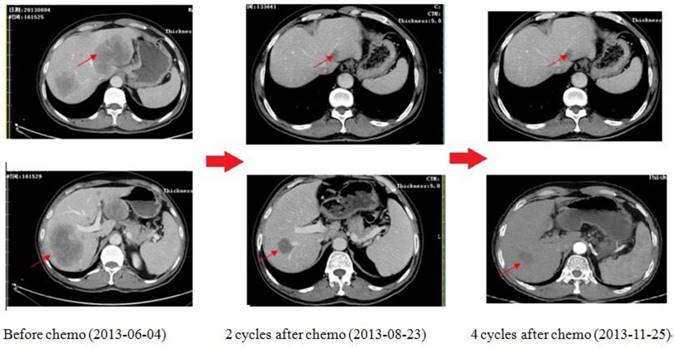

As shown in Figure 6, this is one of the patients who get survival benefit from the individualized chemotherapy based on plasma gene detection. A 59-year-old man was diagnosed as low differentiation adenocarcinoma of stomach by upper-gastrointestinal (GI) endoscopy on 11th march, 2013, during which an irregular ulcera with the length of 2.7*3.1cm at the cardiac wall was noted. As the same time, more than one liver metastasis were confirmed by both type-B ultrasonic exam and CT scan with the biggest one 9.6cm in diameters. Examination of a biopsy specimen led to the diagnosis, and HER2 immunohisto-chemistry (IHC) showed negative. Obviously, the tumor was considered unresectable. We did plasma gene detection for this patient. As a result, plasma BRCA1 was low expressed (1.27, following the cut-off of Table 3), TS was high expressed (1.06, following the cut-off of table 6) while TOPO1 was low expressed (0.25, following the cut-off of Table 3). Therefore, the chemo strategy for this patient was Oxaliplatin plus S-1(Oxaliplatin 85mg/m2, VD, d1,15, S-1 40mg/m2, bid, po, d1-14, q28d). As shown by CT scan, there was partial remission after 2 cycles of chemotherapy with diameter of the biggest one from 9.6cm to 3.5cm. 4 cycles later, the disease as well controlled. 6 cycles later, GI endoscopy showed complete remission of tumor in stomach; while CT scan showed metastatic tumor in liver was stable with the longest diameter of 2.6cm. Then radiation therapy was given on the tumor of liver. After radiation, the patient was followed up and was still in good condition now.

Figure 6

The CT scan of the patient received chemotherapy according to his plasma gene detection. There was partial remission after 2 cycles of chemotherapy. 4 cycles later, the disease was well controlled.